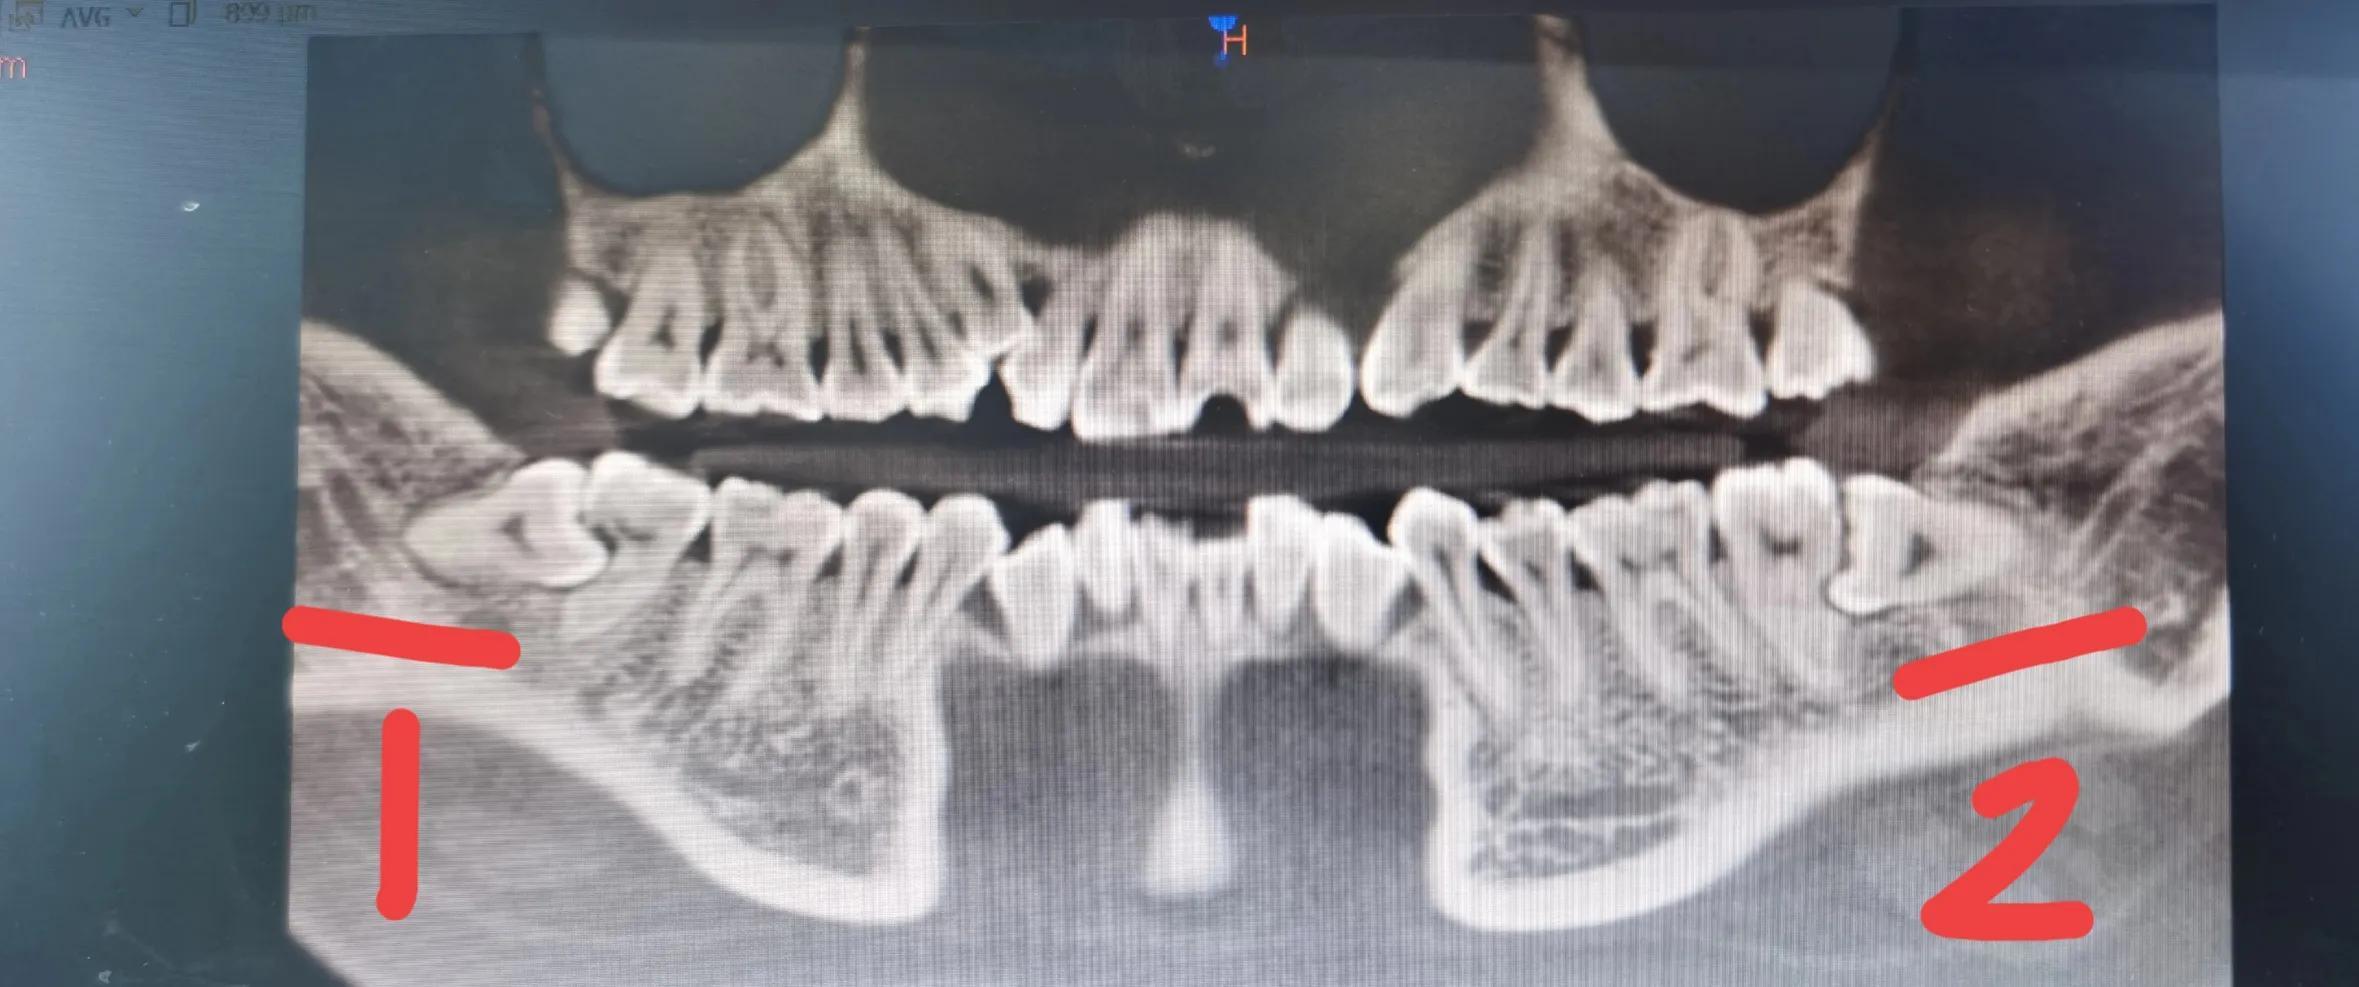

目前这两颗都已拔掉

最后还重新拍了片进行复查,看有没有多余的碎牙齿没有拔出,结果拔的很干净。后来我去药店买了消炎药和奥硝唑片,也备了一些止疼药,但是止疼药从来没用过。